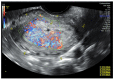

Endometrial cancer (EC) rarely develops in young women. Most cases are associated with known risk factors: BMI > 30, history of Polycystic Ovary Syndrome (PCOs), and race differentiation. The molecular EC classification based on The Cancer Genome Atlas Research Network divides these heterogeneous cancers into four types: Polymerase Epsilon Mutation (POLE), Microsatellite Instability (MSI), Copy Number Low (CNL), and Copy Number High (CNH). This division was introduced to allow for early assessment of neoplastic changes and clinical management, including targeted therapies. The basic technique for imaging endometrium changes is transvaginal sonography. Hysteroscopy is the standard for obtaining endometrial material for histological evaluation. The MRI result permits assessment of the extent of EC cancer infiltration. In young women who want to preserve fertility, apart from surgery, conservative management is often implemented after strict selection based on clinical and pathological data. This pharmacological treatment involves the administration of progestogens MPA (medroxyprogesterone acetate) and MA (megestrol acetate). The use of metformin may increase the effectiveness of such treatment. An alternative option is to apply progestogens locally—via the levonorgestrel-releasing intrauterine device. In addition to pharmacological treatment, hysteroscopic resection may be used—part of the uterine muscle adjacent to the pathologically changed endometrium may also undergo resection. An alternative is the administration of estrogen receptor modulators (e.g., SERMs) or aromatase inhibitors, or GnRH agonists.